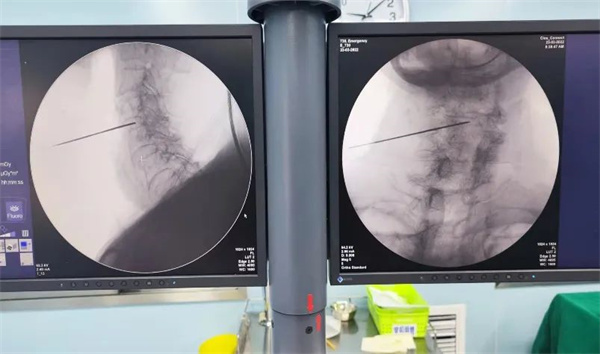

手术如期进行,骨科王辉大夫在C臂引导下熟练地将低温等离子射频刀头置入腰5-骶1椎间盘,进行汽化、消融及成形,手术仅用30分钟便顺利完成,术中未出血,术后仅留有一细小穿刺孔。患者术后即感腰部疼痛消失,活动自如,并于次日出院。

3、拔出针芯,置入腰椎专用等离子刀头,在C臂透视下,仔细确认刀头的位置后,对椎间盘进行消融。